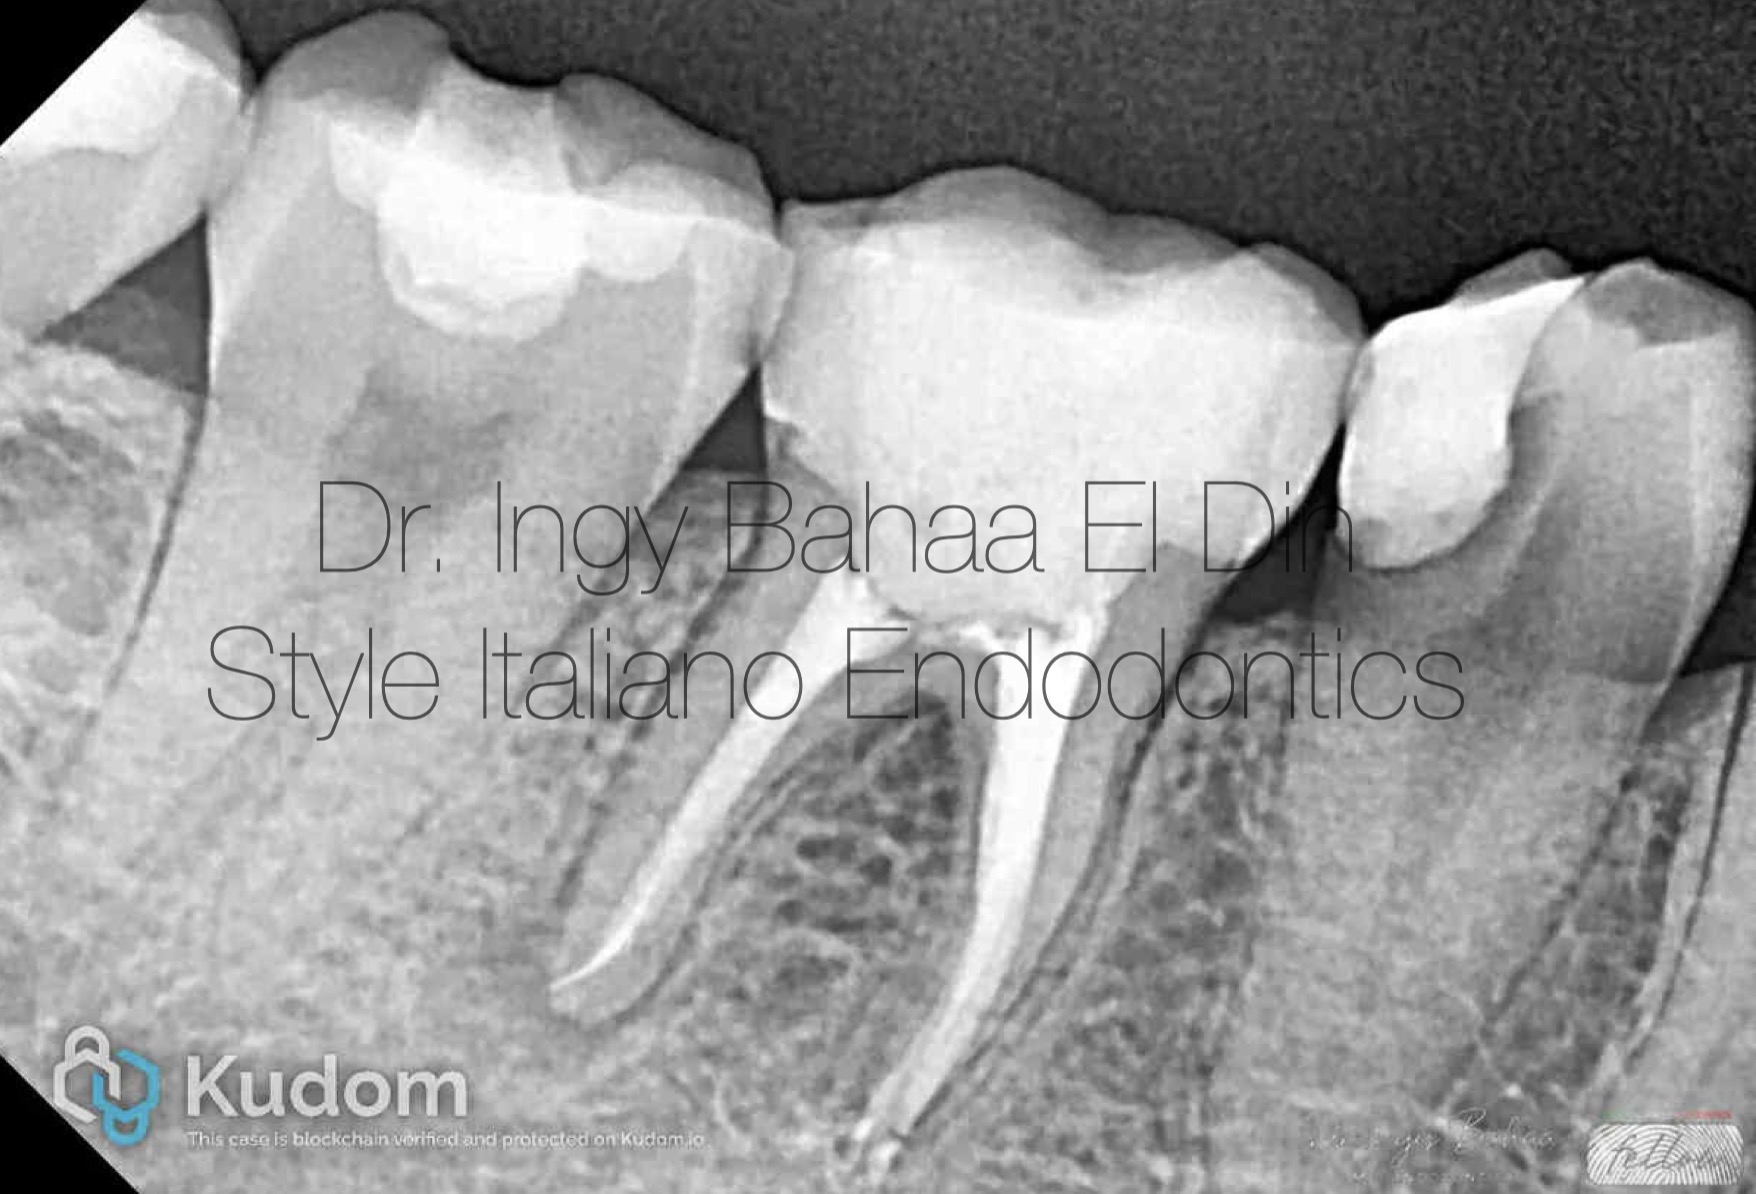

Fig. 1

Case: Referred 25 years old patient came to our clinic with pain on Biting related to lower right first molar , stating a previous endodontic treatment done a year ago with pain on biting ever since. A Periapical Radiographic Xray ( fig1 ) showed obvious widening in lamina dura around mesial and distal root and mild abscesses related to mesial and distal roots .

Two Broken files are also noticed:

One in Mesiobuccal Canal (Middle zone )

And One in Distal Canal (apical zone )

As well as over obturation from ML canal

Cone Beam CT was requested to further locate the broken files